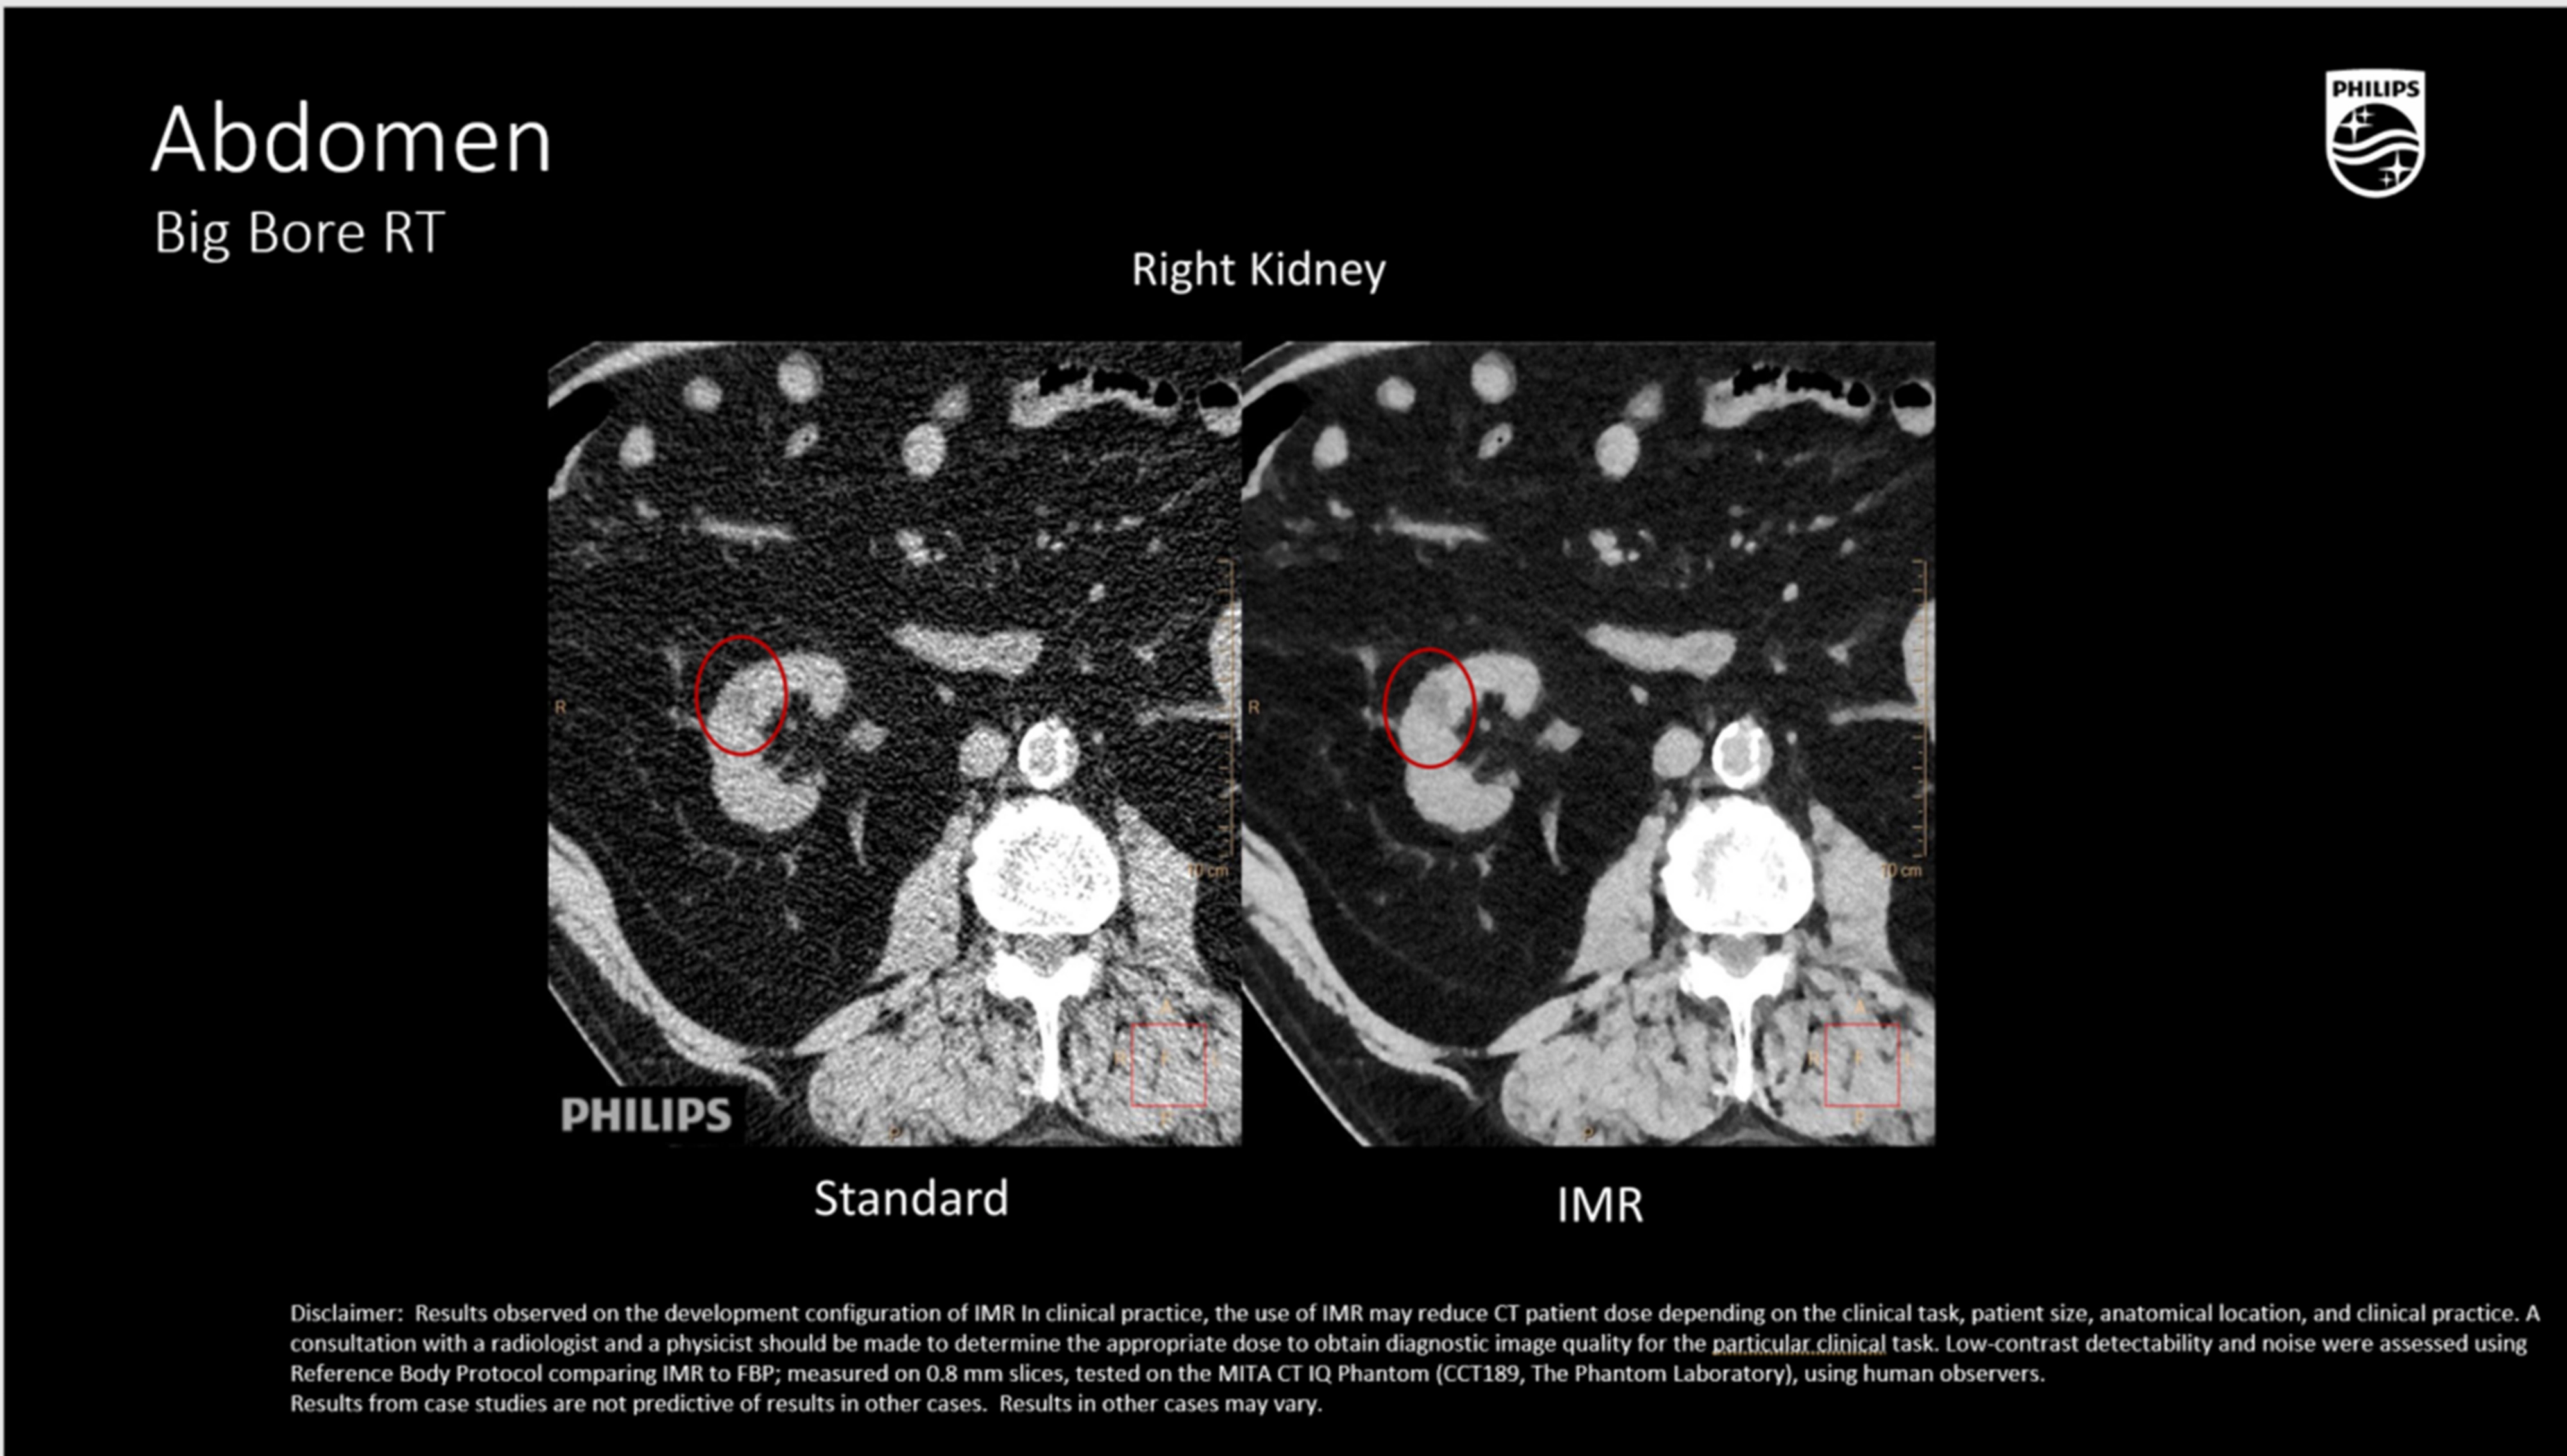

Ключевые технологии визуализации и реконструкции

iDose⁴ (Iterative Dose Reduction Technology)

- Гибридная итеративная реконструкция в проекционном и изображен ческом пространстве повышает качество изображения и устраняет артефакты.

- Повышает контрастно-шумовое соотношение (CNR), снижая лучевую нагрузку на 50–80% при сохранении пространственного разрешения

Абдоминальная и тазовая локализация

- Визуализация мягкотканных опухолей (печень, почка, поджелудочная железа, органы таза) с контурированием OAR,